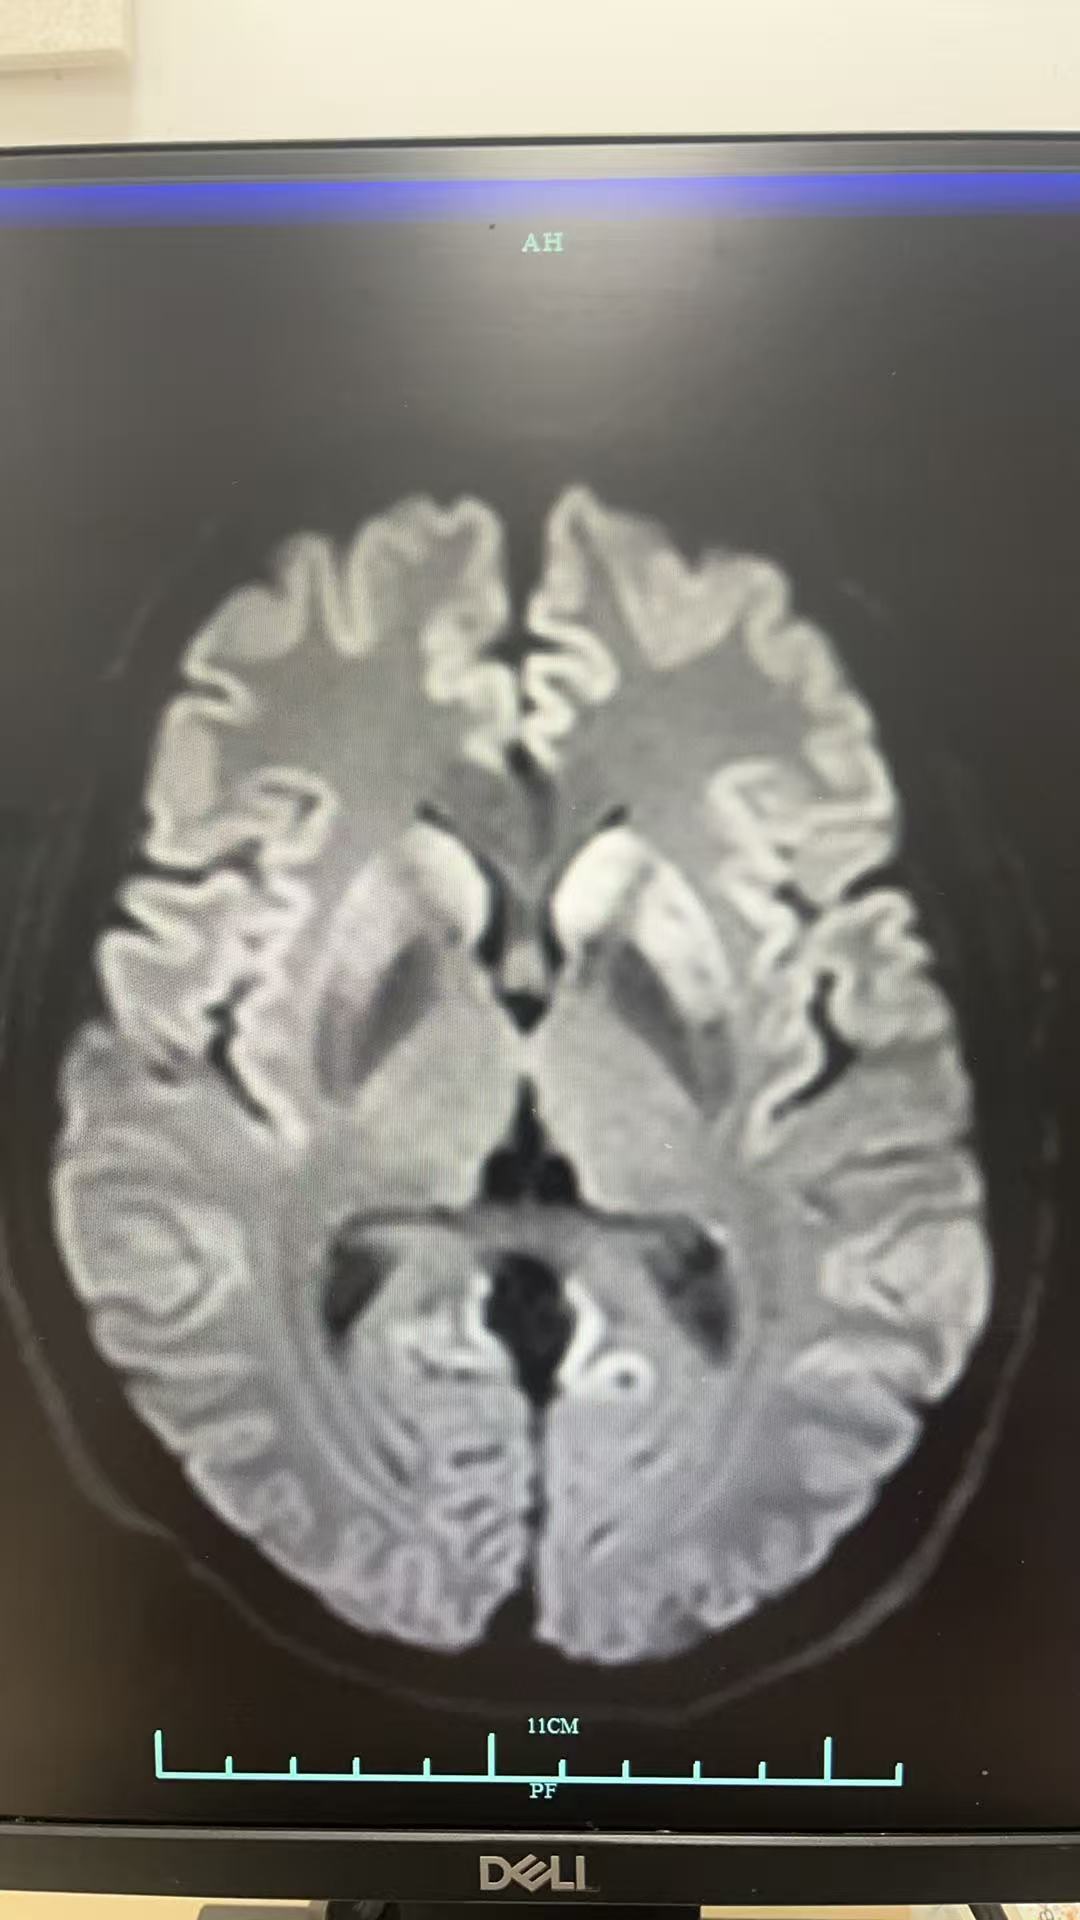

神经内科梁主任会诊后认为:患者二月前出现头晕,症状加重,一月前出现精神症状当地头颅MRI示左侧尾状核和枕叶DWI高信号,本院复诊尚可见硬脑膜强化意见,建议床边脑电图,复查腰穿查脑脊液RTQUICE排除克雅氏病可能。查血LGI1抗体,继续甲强龙治疗。随后送的LGI1抗体结果阴性,而脑脊液的RT-QuIC结果为阳性,因此诊断为克雅病。

本案例的突破点在于病史+脑MRI检查结果,对比指南可以看到我们的MRI在尾状核那边也有明显强化的表现。